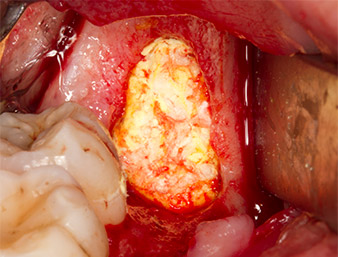

El tejido situado por encima del resto radicular no se había osificado por completo y constaba en su mayor parte de un tejido granulado con alteraciones inflamatorias (figura 4).

Con el fin de obtener material autógeno para el tratamiento posterior de la herida, se utilizó un inserto piezoquirúrgico (Piezomed B5) para obtener virutas de hueso sano del entorno del resto radicular (figura 5).

tejido granulado

Imagen 4: Dos ganchos de Langenbeck y un raspador según Prichard exponen el campo quirúrgico. Se distingue un tejido granulado de la primera osteotomía que no ha cicatrizado en su totalidad.